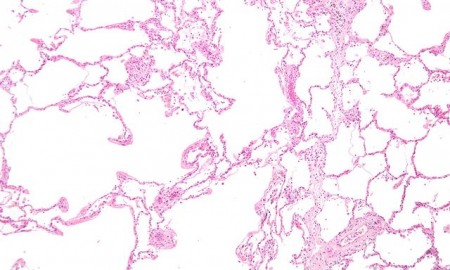

A asma é considerada uma síndrome inflamatória pulmonar crônica que em sua forma clássica está associada com o descontrole das atividades de células T helper 2 (Th2).

Modelos murinos têm sido desenvolvidos para estudar os mecanismos da asma, sendo a ovoalbumina (OVA) o alérgeno mais utilizado. Entretanto, segundo Russo, a OVA é um alérgeno alimentar e não respiratório. Por isso, modelos experimentais de alergias pulmonares foram adaptados para alérgenos respiratórios como os derivados de ácaros encontrados na poeira doméstica.

No Brasil, um dos ácaros mais prevalentes é o Blomia tropicalis (Bt). Recentemente, informa Russo, o grupo de pesquisa desenvolveu um modelo de asma alérgica utilizando extratos de Bt. Em trabalhos anteriores com o modelo OVA, o grupo mostrou que a ativação do sistema imune por agonistas de receptores Toll-like (TLRs) é um mecanismo imunológico potente para atenuar as reações alérgicas.